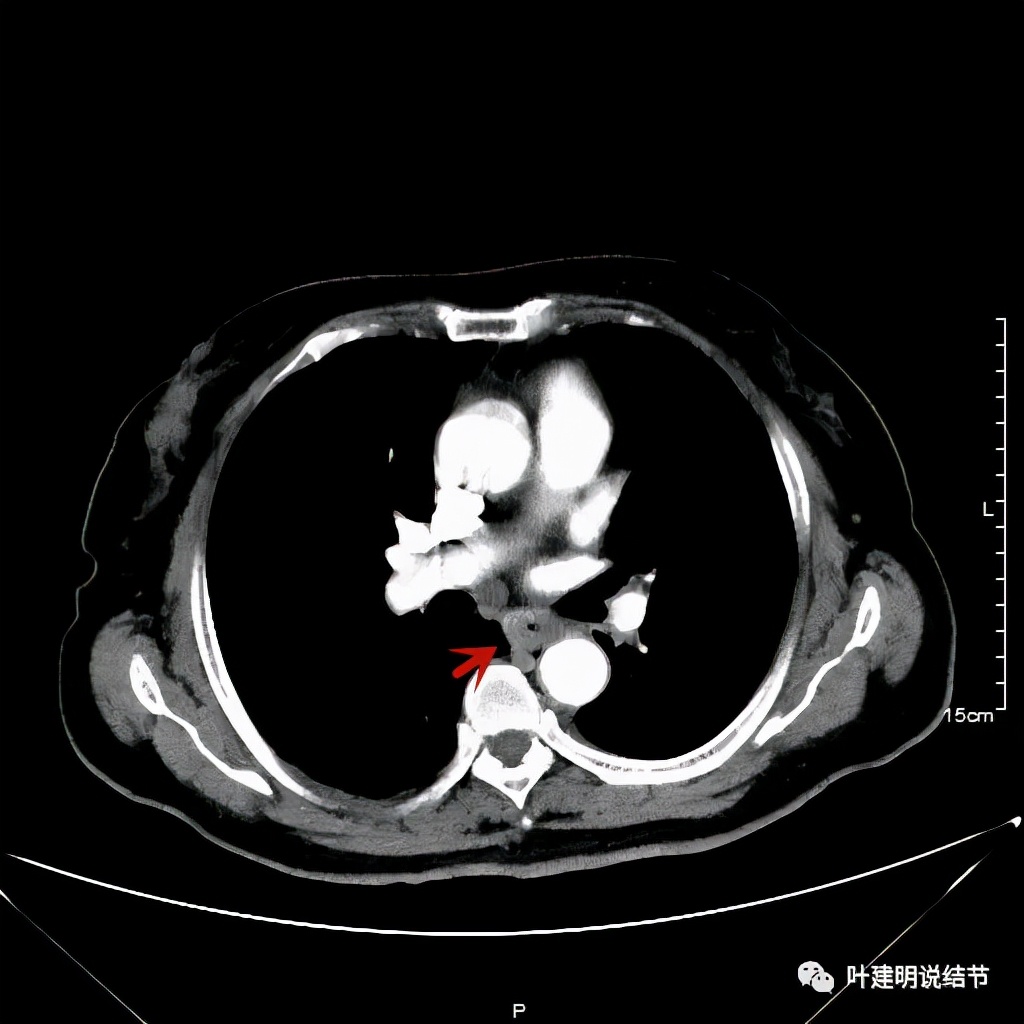

她是食管中分化鳞癌,但有腹部广泛的占位性病变,当初还以为是淋巴瘤,因为我们了几乎没有见过食管癌这种转移样子的。予以的治疗方案是“特瑞普利单抗+多西他赛+卡铂”免疫加化疗3次,后因患者不愿意继续化疗,仅予以特瑞普利单抗单药维持。我们再来看她刚发现时的胸部CT以及腹部CT增强的情况:

其实胸部CT示食管的病变感觉并不厉害,外侵或纵隔内转移均不明显,但其腹部的CT让人大吃一惊!

上图是初发现时的CT影像报告,其他CT图像上红色箭头所指范围内都是肿瘤,整合成团,挤压血管以及正常器官结构。你有见过原发灶这么不显眼,而腹部转移灶这么厉害的食管癌吗?但经过穿刺证实是转移性鳞癌,结合病史考虑是食管癌转移。手术自然是不可能了根治了,放疗也不合适,经过MDT并与患方充分沟通,依据食管癌治疗指南: